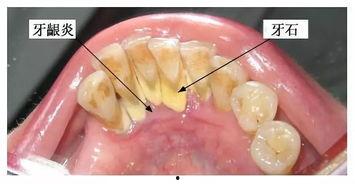

你知道吗,洗牙其实就像给牙齿做了一次彻底的SPA呢!想象那些藏在牙缝里的污垢、牙菌斑,还有那些顽固的牙结石,全都被洗牙师用专业的工具给清理干净了。这样一来,你的牙齿不仅会焕然一新,还能预防各种口腔疾病呢!

1. 预防牙周病:牙结石是牙周病的罪魁祸首,洗牙可以有效地去除牙结石,降低牙周病的风险。